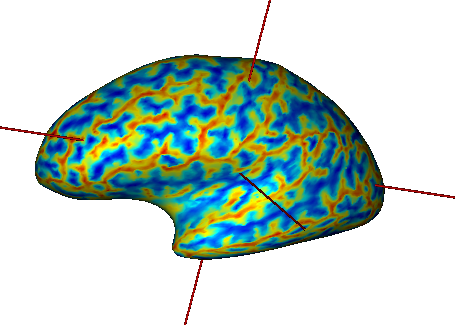

Load:

White matter mesh:

data_for_anatomist/subject01/subject01_Lwhite.meshActivation map:

data_for_anatomist/subject01/Audio-Video_T_map.niiT1 MRI:

data_for_anatomist/subject01/subject01.nii

Change the color palette of the map.

Load referential information from file header for the map and the T1 MRI.

After loading referentials¶

Make a fusion between the mesh and the map (click on

).Select the Fusion3DMethod and click OK. A new FUSION3D object is created.

Place the FUSION3D object into a

.Right-click on the FUSION3D object, then select Fusion => Control 3d fusion.

Select Fusion mode => Linear and Rate = 50.

Fusion between a cortical surface mesh and an activation map¶